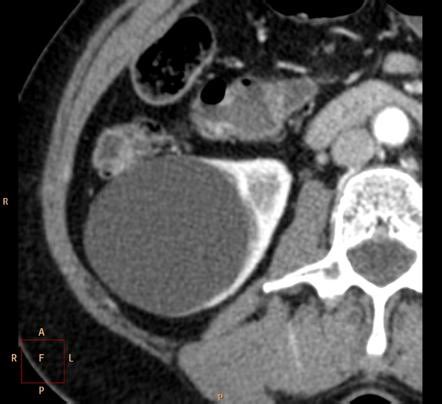

الاسباب :

غير معروفة ، الاصابة بارتفاع ضغط الدم ، قصور وظائف الكلى ، التقدم بالسن ، وفي حالات محدودة تكون باسباب وراثية او التهابات فطرية.

الاعراض : في الغالب بدون اعراض ، الم متقطع بالخاصرة او الجنب ، وفي حالات متقدمة ونادرة قد يكون دم بالبول

الخيار العلاجي يعتمد على نوع الكيس ودرجته ، حجم الكيس ، صحة المريض العامة ، الاعراض ، سبب الكيس اذا كان التهاب او غيره

فممكن كيس من نفس الدرجة في شخصين مختلفين يعالج بطريقتين مختلفة بناء على العوامل السابقة.